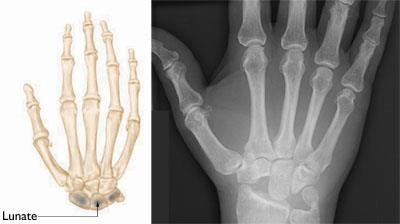

Normal anatomy of the hand and wrist

Normal skeletal anatomy of the hand and wrist. The lunate is one of the small bones in the wrist.

Reproduced and modified with permission from JF Sarwark, ed: Essentials of Musculoskeletal Care, ed 4. Rosemont, IL, American Academy of Orthopaedic Surgeons, 2010.